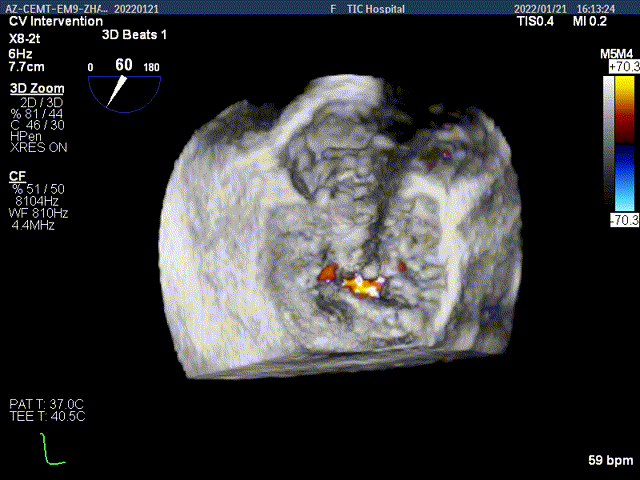

3D-color MV view:大量反流,起源于2区

Color-view:大量反流,主要血流PISA来源于2区

患者麻醉方式为全麻,建立静脉通路后,穿刺右侧股静脉,预埋ProGlide缝合器,食道超声指导下房间隔穿刺成功,将Superstiff导丝送至左房,应用18F鞘管扩张穿刺部位,沿导丝将导引导管送入左房,经导管鞘系统将NovoClasp瓣膜夹顺利到达二尖瓣目标位置,在食道超声辅助下,将成形夹精确定位后,使用1个宽的clip(MCD0101)成功夹合二尖瓣A2-P2区,彩色多普勒超声(2D+3D)显示微少量残余分流,整体反流量改善2级以上,后多切面证实夹合组织充分,肺静脉多普勒波形由反向恢复正常,手术顺利结束,安返普通病房。

3D视图下夹子对准最大反流束进入左室

X-plane:下夹子尝试先捕获2区偏内侧瓣叶

该位置夹合后,Color提示内侧区域残余反流较多

打开夹子,并移动到2区偏外侧区域进行夹合

内侧区域残余反流减少